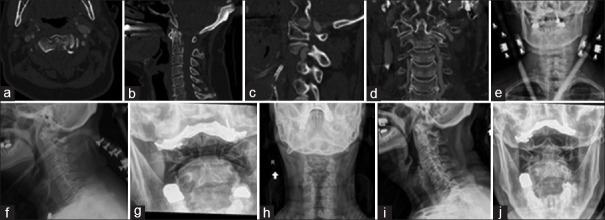

Results: A total of 54 patients were included for analysis. The average time spent in a halo vest was 2.69 (0.58) months, and the average time to final follow-up was 5.49 (5.84) months. The most common fracture morphologies were the Hangman variant (29.6%) and type III odontoid (29.6%). Forty-nine patients (94.2%) out of 52 patients considered were successfully treated as defined by the lack of need for surgical intervention. Three patients (5.6%) experienced medical complications; two of the three patients died within 30 days of HVI. Lastly, 18 patients (33.3%) experienced HVI instrumentation-related complications, the most common of which was loose halo pins (13.0%).

Conclusion: HVI is associated with lower morbidity and mortality in elderly patients than previously reported and thus may be safely used in this population. However, providers should be mindful of initial clinical presentation and underlying comorbidities when weighing between surgical and nonsurgical intervention.